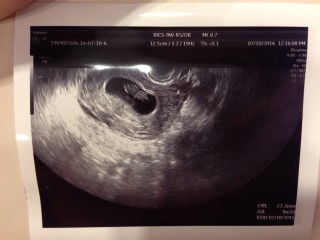

一週間前より頭や手足がはっきりしてきました! 撮影中なかなか動かないな、と先生と画面 ガン見してたら急に頭がピコピコ上下して、 うごうごしてました!可愛いかったです。

特につわりがなくて検診までは無事に育ってくれているのか不安でいっぱいでしたが、ちゃんと二頭身に成長してくれていて安心しました! 大きさは22.9mmで先生にも標準サイズで元気に育ってますねと言われて嬉しかったです☆

左上が頭でこれ手と足!と言われ確認できました。足がぴょこぴょこ動いててかわいかったです。CRL23ミリ。順調に育ってくれています!